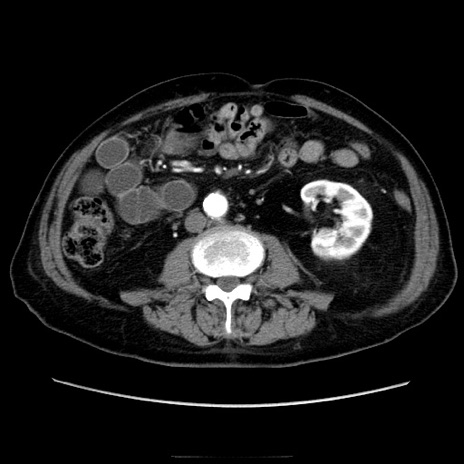

冠状断像

【症例】70歳代男性

【主訴】腹痛

【現病歴】肝硬変・肝細胞癌にてかかりつけの方。約9時間前に食後より腹痛出現。症状が徐々に増悪し、嘔吐出現したため来院。

【既往歴】肝硬変、肝細胞癌(RFA、TACE後)

【身体所見】意識清明、表情苦悶様、BT 36℃、BP 129/78mmHg、P 88bpm、SpO2 97%(RA)、右上腹部から心窩部にかけて圧痛あり、反跳痛なし、筋性防御あり。

【データ】WBC 5800、CRP 0.16